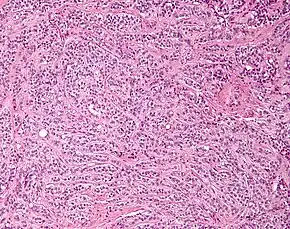

| Micrograph of a Sertoli cell tumour. H&E stain. | |

A Sertoli cell tumour, also Sertoli cell tumor (US spelling), is a sex cord-gonadal stromal tumor of Sertoli cells. They can occur in the testis or ovary. They are very rare and generally peak between the ages of 35 and 50. They are typically well-differentiated, and may be misdiagnosed as seminomas as they often appear very similar.[1]

Microscopy and immunohistochemistry are the only way to give a definitive diagnosis, especially when there is a suspected seminoma.[3]